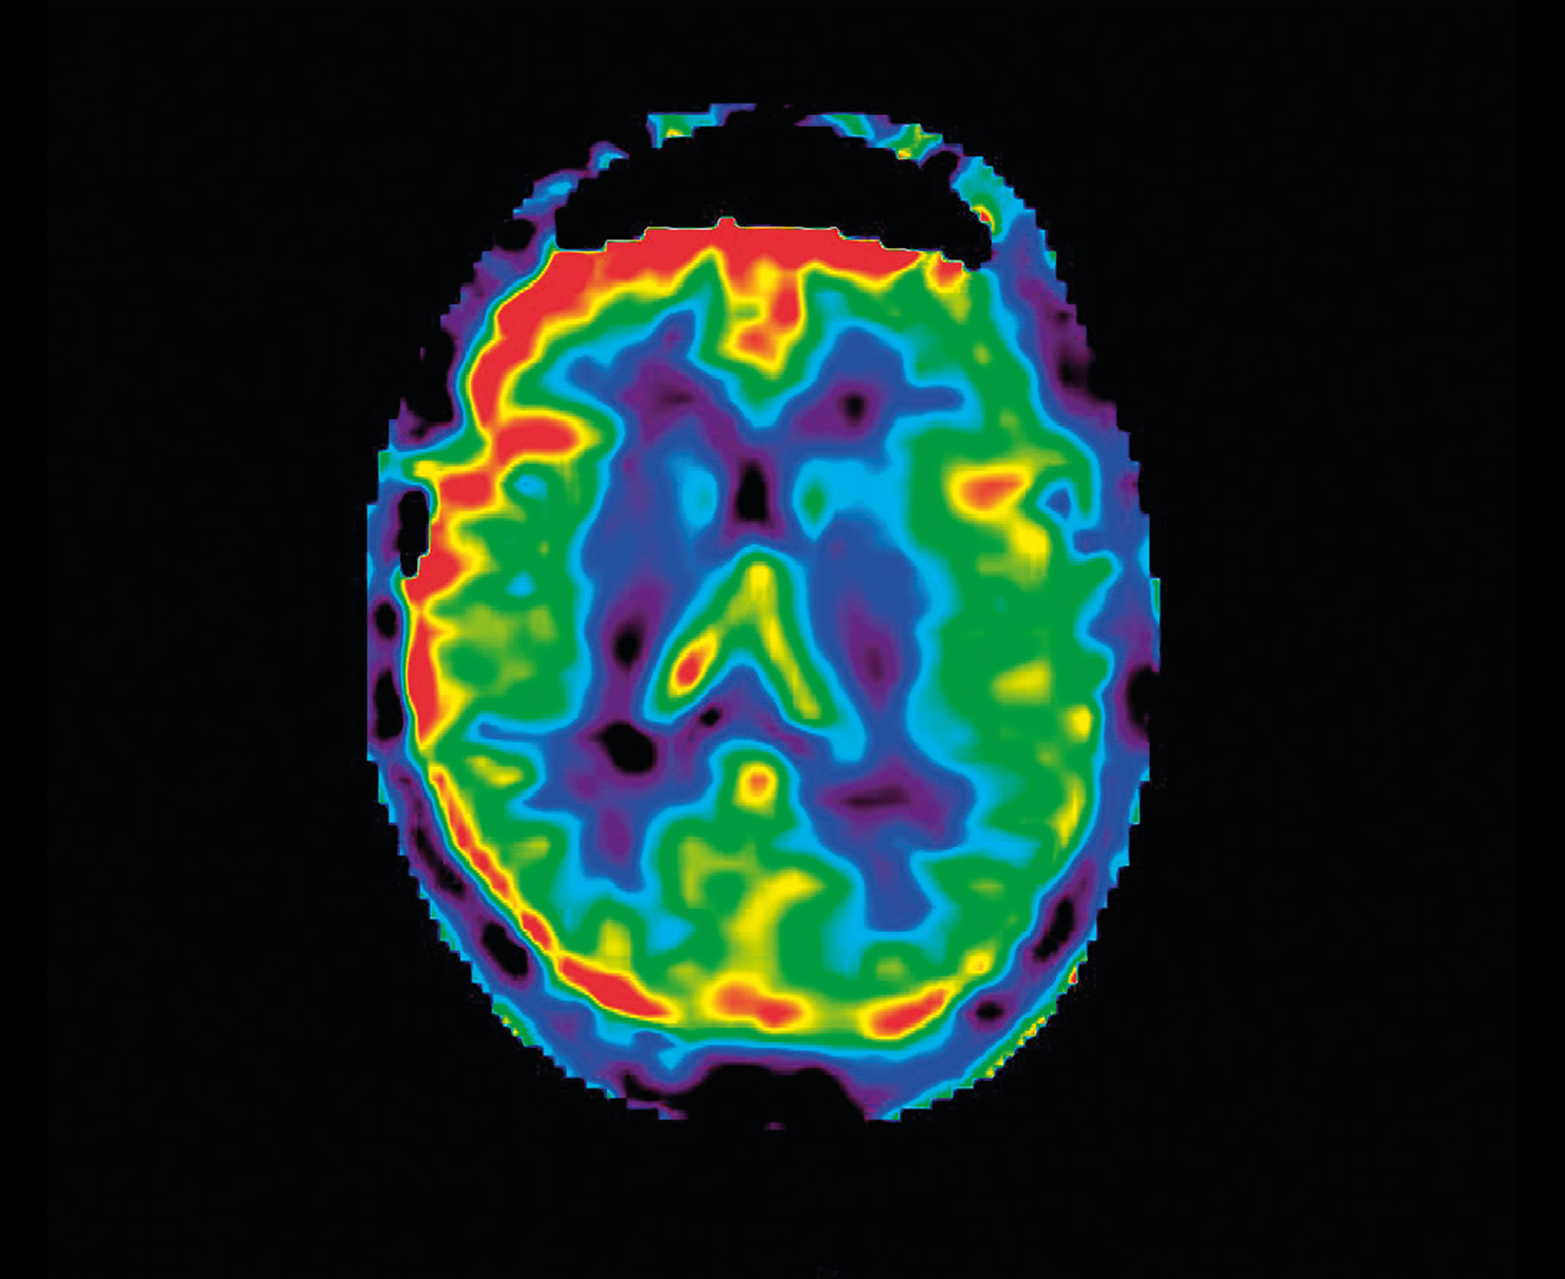

- Неинвазивная перфузия ASL для педиатрии и противопоказания почек

Неконтрастная перфузия ASL